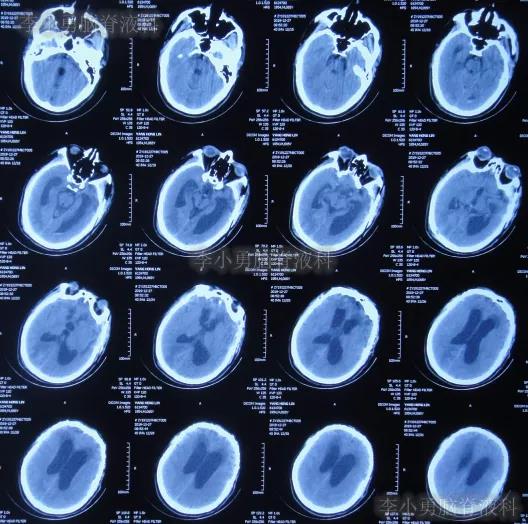

2019年10月20日患者骑电动车在马路上行驶时被大货车撞倒,当时意识清楚,只感到有些头晕,未在意就自行回家,但回家后约3-4小时出现头晕加重,并伴有恶心呕吐的症状,家人急送到当地的河北省邯郸市某医院,查头颅CT示脑出血(图-1);既往病史2015年曾因头部外伤致硬膜下血肿,进行了钻孔引流术。

图-1:2019年10月20日头颅CT

急诊进行了开颅去骨瓣血肿清除术,术后次日查头颅CT示去骨瓣术后(图-2)。

图-2:2019年10月21日头颅CT